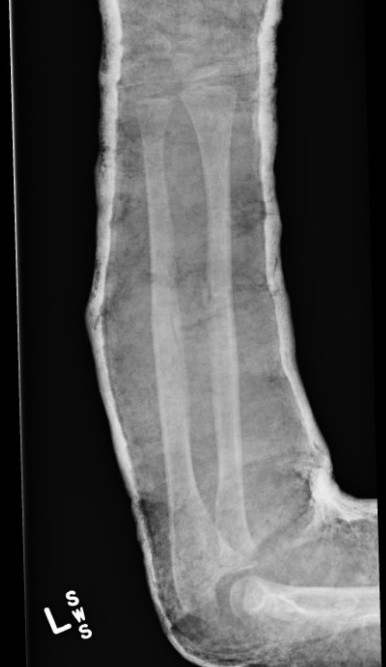

3. Intramedullary elastic nail

TENS technique

Technique

Radius (typically first as more difficult to reduce)

Entry point with awl 2 cm proximal to distal physis

1. Radial styloid / distal lateral entry

- ensure radial nerve / cephalic vein, 1st extensor compartment protected

2. Listers tubercle / dorsal entry

Elastic Nail size

60 - 70% of the intramedullary canal

Typically 1.5 - 2.5 mm

Fracture reduction

Avoid passing nails incorrectly multiple times as may cause compartment syndrome

Bend tip of elastic nail

May need small open reduction

Cut nail

Withdraw 1 cm, cut with endcutter, then advance

Ulna (usually reduced after radius fixation)

Entry point 2 cm distal to apophyseal plate

1. Proximal lateral

- avoids ulna nerve

3. Distal medial

Postoperative

Cast in supination to tighten interosseous membrane

Cast 6 weeks

Removal of TENS at 4 - 6 months once osseous union established